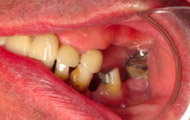

Exemple de 3 dents manquantes remplacées par 3 couronnes sur implants.

Pose des piliers prothétiques et des 3 couronnes scellées.

Situation clinique initiale

Situation clinique terminée